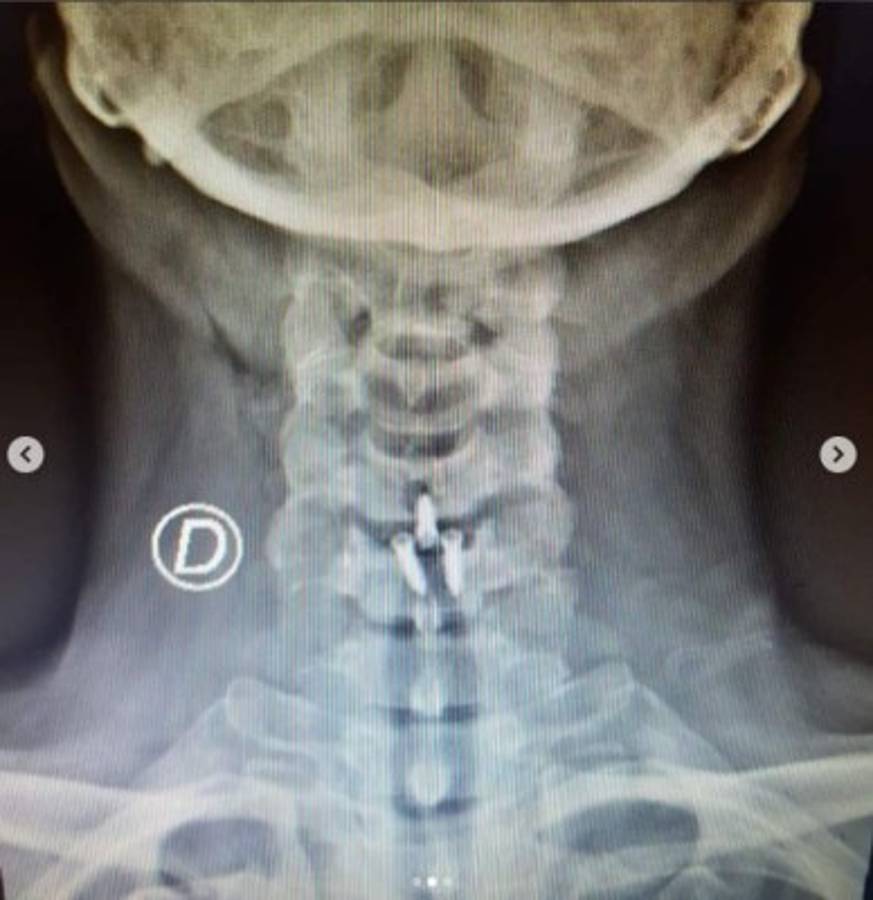

CIUDAD DE MÉXICO, MÉXICO.- El actor mexicano Arath de la Torre fue sometido recientemente a una cirugía de emergencia. A través de sus redes sociales informó a sus seguidores que fue operado de una hernia de disco cervical que lo hizo enfrentar terribles dolencias durante años.

'Fui intervenido de una hernia de disco cervical, estoy en perfectas condiciones, a pesar de haber sido un accidente (caída), fue programada para el 26 de septiembre para poder darle colchón a 'Mi marido tiene más familia' y cumplir con otros compromisos laborales. Esta es la verdad y no se dejen llevar. Estaré de regreso en la telenovela en dos semanas y no salgo de la misma. Gracias a mi Neurocirujano y a todo su equipo. Viva la vida', escribió en Instagram.

Así mostró su operación a los seguidores de Instagram. Foto @arathdelatorre